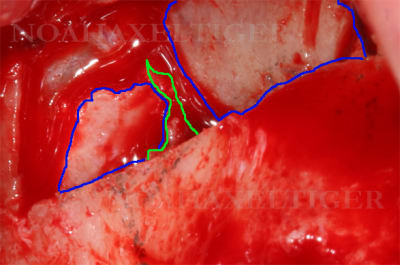

Tout à fait d'accord avec toi. Comme dans le cas suivant ou avec le piézo j'ai découpé 2 fenetres latérales de part et d'autre du septum que j'ai ensuite refoulées dans le sinus après élévation de la membrane de Schneider. Mise en place de mon implant dans le septum puis comblement sinusien classique.